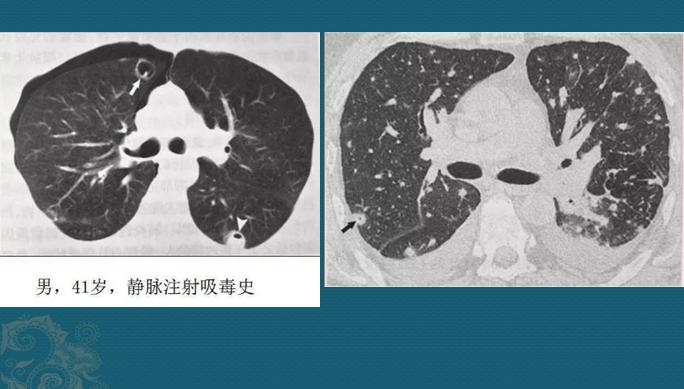

狡猾的金葡菌还有血源性感染

血源性的通常比较重!金葡菌一旦得势,形成局部脓肿大量繁殖,细菌入血,就像野草种子一样,随血液可以到达全身任何部位,常见的有骨髓、关节、大脑、双肺、肾脏等。

如果它们抵达肺部小血管周围生根发芽,就会制造各种毒素引发炎症,表现为多发点片状影或类圆形结节影,边缘清晰或模糊,沿支气管血管束或肺外周和基底部分布,因为是化脓性感染,多数结节最后会坏死、液化,形成空洞,当损伤血管或者形成血管内菌栓堵塞还可以引起远侧肺组织缺血坏死(肺梗死),形成胸膜下楔形肺实变影。

血源性金葡菌肺炎

这些都是金葡菌小草刚发芽,多发小结节、小斑片影,有的形成了小空洞和小气囊,部分与血管关系密切,提示病菌是从血道来源引起肺部播散,及时抗生素治疗可以压制炎症发展。